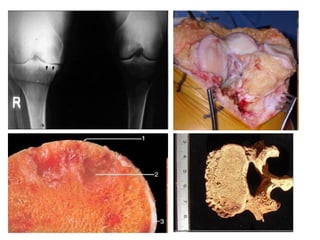

OSTEOSARCOMA

(OSTEOGENIC SARCOMA)

LATE TEENS

KNEES

METAPHYSES

PAINFUL!!!

TYPES of OSTEOSARCOMAS

• • The anatomic portion of the bone from which

they arise (intramedullary, intracortical, or surface)

• • Degree of differentiation

• • Multicentricity (synchronous, metachronous)

• • Primary (underlying bone is unremarkable) or

secondary (e.g., osteosarcoma associated with

pre-existing disorders such as benign tumors,

Paget disease, bone infarcts, previous irradiation)

• • Histologic variants (osteoblastic, chondroblastic,

fibroblastic, telangiectatic, small cell, and giant

cell)

The most common subtype is osteosarcoma that arises in the

metaphysis of long bones; is primary, solitary, intramedullary, and

poorly differentiated; and produces a predominantly bony matrix

OSTEOSARCOMA (OSTEOGENIC SARCOMA) LATE TEENS KNEES METAPHYSES PAINFUL!!!

• 57.

TYPES of OSTEOSARCOMAS • • The anatomic portion of the bone from which they arise (intramedullary, intracortical, or surface) • • Degree of differentiation • • Multicentricity (synchronous, metachronous) • • Primary (underlying bone is unremarkable) or secondary (e.g., osteosarcoma associated with pre-existing disorders such as benign tumors, Paget disease, bone infarcts, previous irradiation) • • Histologic variants (osteoblastic, chondroblastic, fibroblastic, telangiectatic, small cell, and giant cell)

• 58.

The most commonsubtype is osteosarcoma that arises in the metaphysis of long bones; is primary, solitary, intramedullary, and poorly differentiated; and produces a predominantly bony matrix